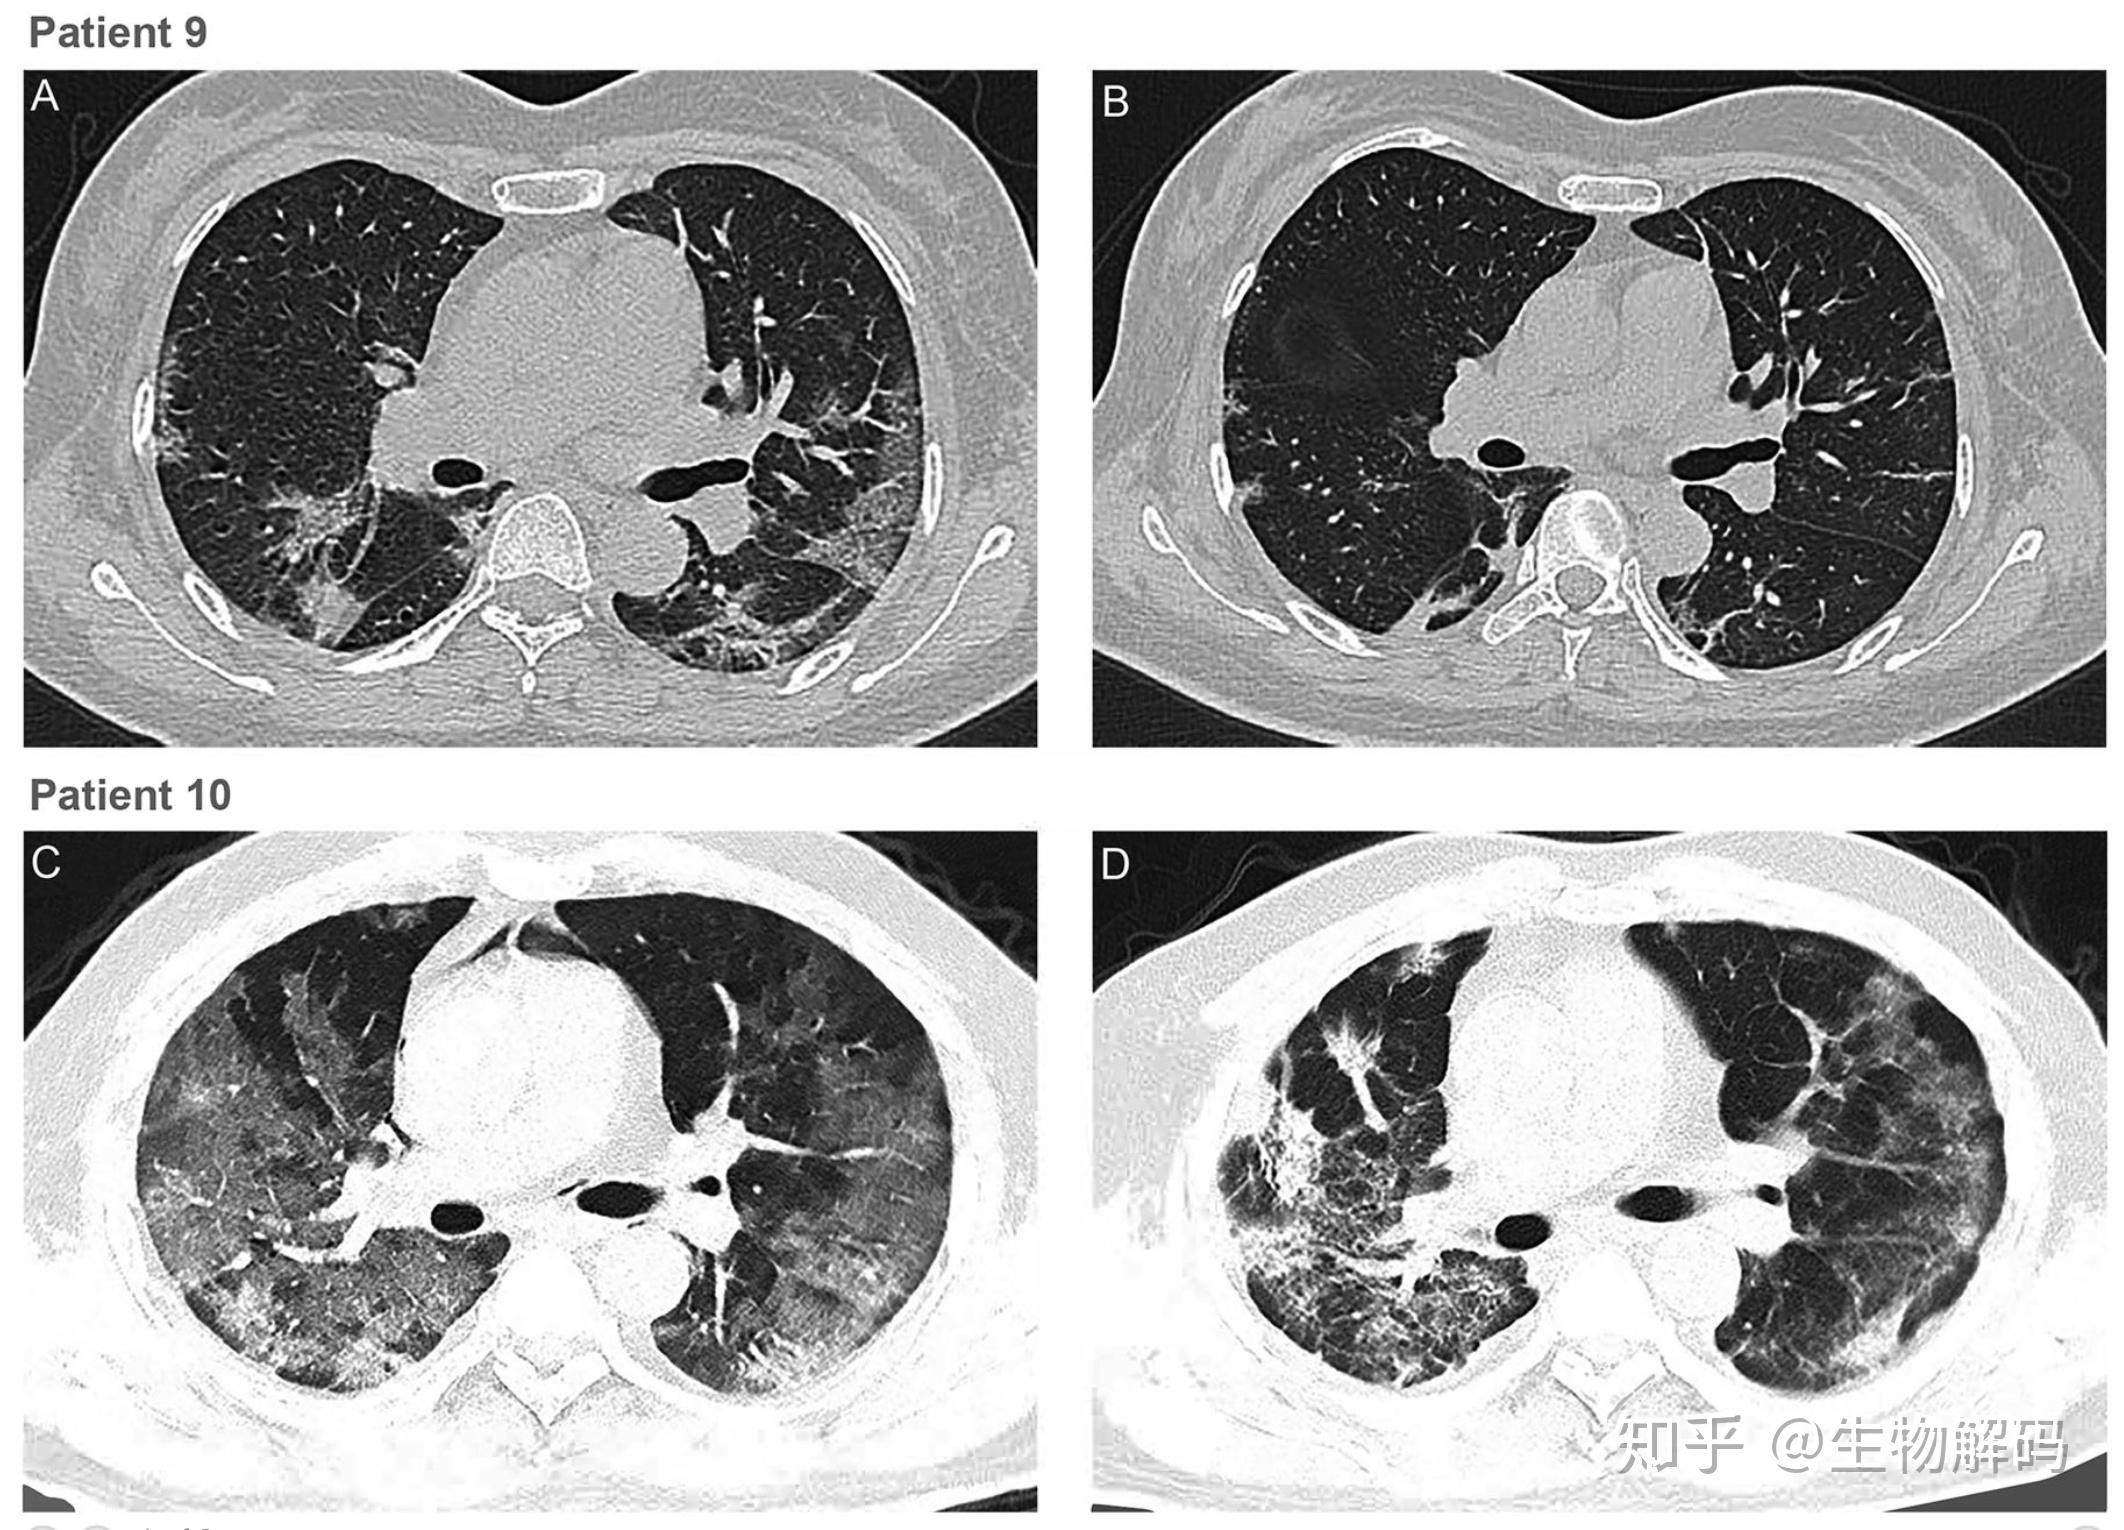

在这项工作中,作者探索了恢复性血浆(convalescent plasma)输血抢救